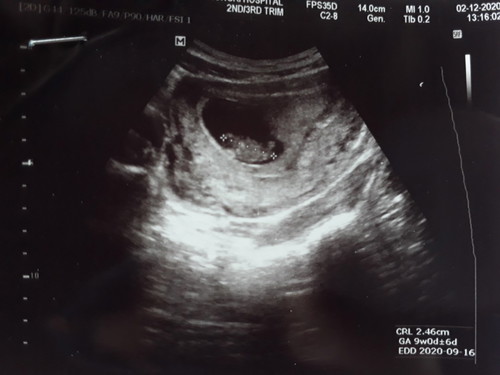

กำหนดคลอดเดือนกันยา วันนี้ไปซาวด์กับลุงหมอมา ลุงหมอบอกว่า แม่ท้องเล็กแต่หนูตัวใหญ่ดี หนูเอาหัวลงอุ้งเชิงกรานอยู่ในท่าเตรียมตัวคลอดแล้ว ลุงหมอบอกกลางเดือนหน้าเตรียมตัวไว้เลย ตอนนี้พยายามเดิน ยืน นั่ง ให้น้อยที่สุด เพราะกลัวคลอดก่อนกำหนด หนูเอาหัวลงต่ำมากแล้ว อยากออกมาหาแม่แล้วค่ะ #คุณแม่เลี้ยงเดี่ยว ✌️✌️🥰